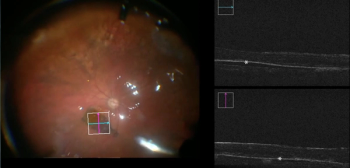

Heads-up surgery is moving into the next generation of vitreoretinal surgery, with novel technologies being developed for surgeons.

S.K. Steven Houston III, MD, discusses retina innovations in use in his practice, including the NGENUITY 1.4 upgrade from Alcon, and adapting to ever-changing operating room spacing and set-up in the COVID-19 environment